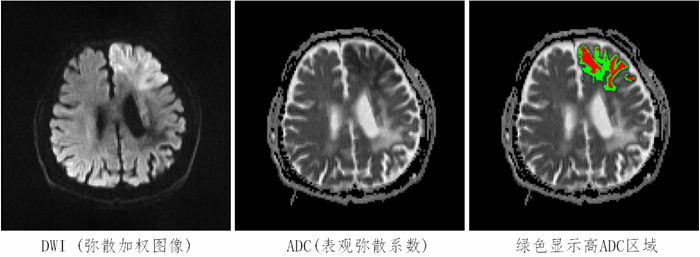

医学图像与数字手术研究室研究小组经过多年研究积累发现,有一类脑卒中病人,其由弥散加权图像确定的梗死要远大于由表观弥散系数确定的梗死;该类病人是最适合溶栓的病人,经过溶栓而有好预后的几率要提高35倍;与现有的基于弥散-灌注失配选择溶栓病人方法相比,出现好预后的几率高达8倍。该成果被《柳叶刀》(Lancet )录用为“柳叶刀-中国医科院2015年健康高峰论坛”成果并公开发表。

彩色区域为自动确定的缺血区域,高ADC区域占的比例达55%,病人溶栓后有好预后